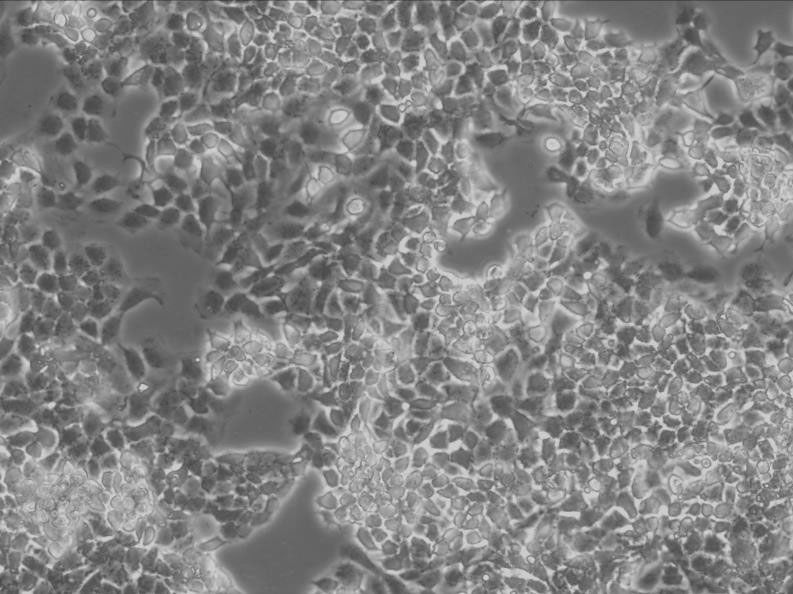

细胞背景资料:该细胞来源于一名低分化胃癌患者的转移性腹水,1987年分离建立。该细胞表达CEA和TAG-72。

细胞形态:上皮细胞样

细胞生长:贴壁

细胞生长特性:多细胞聚集、悬浮生长